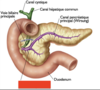

28

Grand omentum

29

**A. gastrique g.**

(la petite courbure de l’estomac et une partie de l’œsophage abdominal)

30

**A. splénique**

Pour la rate, une partie du pancréas et donne l’a. gastro-épiploïque G pour la grande courbure de l’estoma

31

A. hépatique commun

32

A. hépatique propre

branch of the CHA that goes up

**main divisions:**